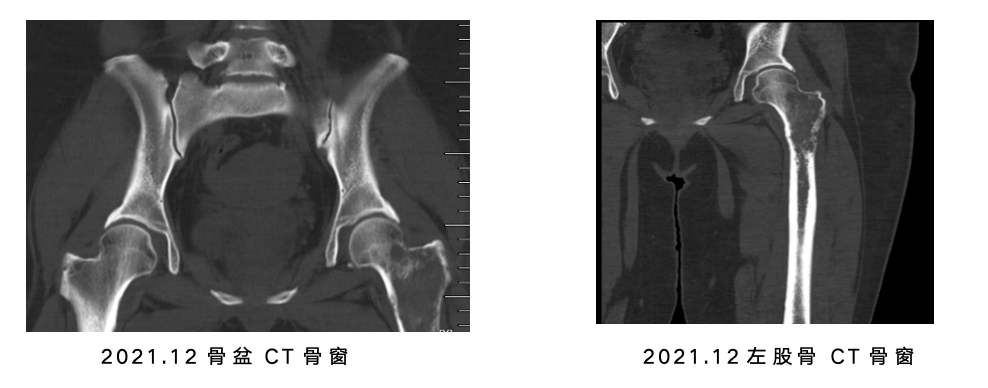

• 骨盆及左股骨CT(含CT骨窗):左侧股骨见溶骨性破坏,左股骨上段为著。

图片

患者左侧股骨转移灶为溶骨性破坏,活动严重受限,疼痛显著且伴有高骨折风险。根据共识,对承重骨有症状或结构不稳定的转移灶,应积极进行局部治疗。本例选择局部放疗,有效缓解了疼痛,改善了活动能力,并在影像学上观察到成骨修复的表现,证实了放疗在骨转移局部控制中的重要地位。与此同时,患者接受了骨改良药物地舒单抗,以系统性降低SREs的发生风险。根据相关临床共识,一旦确诊骨转移,无论是否伴有临床症状,均应尽早启动骨改良药物治疗,其核心理念在于对SREs进行早期、主动的预防,而非在并发症发生后再行处理。整体治疗遵循了晚期乳腺癌“全身治疗为主,局部与支持治疗为辅”的核心管理原则。